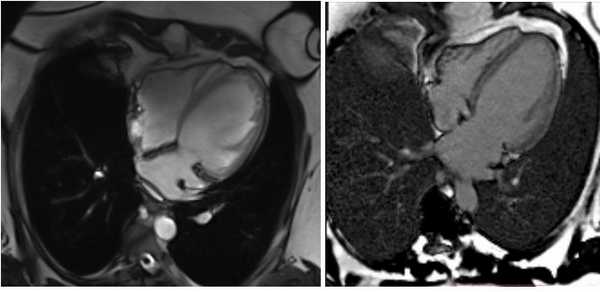

Рисунок 1. МРТ. Четырехкамерное сечение сердца. Стрелкой указан дефект межпредсердной перегородки (ДМПП).

Рисунок 2. МРТ. Аневризма нисходящего отдела аорты.

Рисунок 3. МРТ. Четырехкамерное сечение сердца. Апикальная гипертрофия миокарда левого желудочка.

Рисунок 4. МРТ. Четырехкамерное сечение сердца. Миокардит, субэпикардиальное и интрамиокардиальное накопление контрастного препарата.

Рисунок 5. МРТ. Двухкамерное сечение левого желудочка. Постинфарктный кардиосклероз.